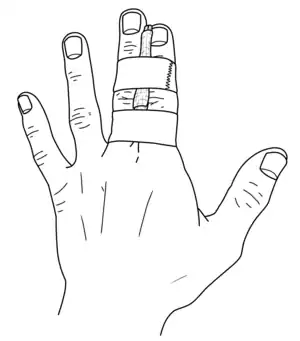

| Treatment | Joint reduction followed by splinting or buddy tapping for few weeks[4][3] |

Treatment is by joint reduction, which can often be achieved by pulling on the finger.[5] This may be carried out following a ring block of the affected finger; though not always required.[5][4] Following reduction X-rays are done to verify success and the finger splinted or buddy tapped for a week or two.[4][3] If splinted, it may be recommended to remove the splint to move the finger daily.[4] When a fracture or instability is also present, management is more complicated.[3] Dislocated fingers are common.[2] They occur most often in the late teenage years.[2]

When the dislocation is backwards, the PIP joint is straightened and the finger is pulled on.[3] When the dislocation is forwards, the PIP joint is bent and the finger is pulled on.[3] In backwards dislocations splinted or buddy tapped for a week or two is generally all that is required.[4][3] A small volar plate fracture (less than 30%) does not generally require a change in treatment, though larger fractures, decreased range of motion, or instability requires hand surgery follow-up.[4] In forwards dislocations splinting for 6 weeks with the finger straight maybe recommended.[4]